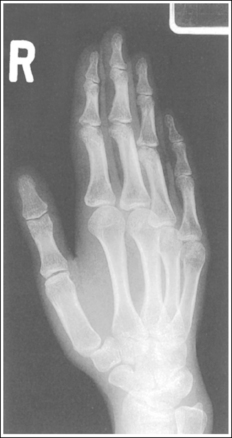

Hand: Posteroanterior Projection

The digits and metacarpals demonstrate a PA projection. The soft tissue outlines of the second through fifth phalanges are uniform, the distance between the metacarpal heads is equal, and the same midshaft concavity is demonstrated on both sides of the phalanges and metacarpals of the second through fifth digits.

• A PA projection of the hand is obtained when the patient fully extends the hand and rests the palmar surface flat against the IR (Figure 4-23).

• PA versus external oblique hand position. If the hand is not fully extended but is slightly flexed, it often relaxes into an external PA oblique projection when it is resting against the IR. A PA oblique hand projection is signified by slight superimposition of the third through fifth metacarpal heads and unequal soft tissue thickness and midshaft concavity on the sides of the phalanges. The metacarpals also show unequal midshaft concavity and spacing (see Image 20). Abducting the patient's arm and placing the forearm and humerus on the same horizontal plane, with the elbow flexed 90 degrees, assists in preventing an externally rotated PA oblique projection and will best demonstrate the wrist. This is important if a wrist condition is causing radiation hand pain. When the patient has been positioned in this manner, the ulnar styloid appears in profile on the image. Internal rotation of the hand is seldom a problem, because the thumb prevents this movement.

Image 20

No soft tissue overlap of adjacent digits is present.

The IP, MP, and CM joints are visible as open spaces, and the phalanges and metacarpals are not foreshortened. The thumb is demonstrated in a 45-degree PA oblique projection.

• When the hand and fingers are fully extended and a perpendicular central ray is centered to the third MP joint space, the IP, MP, and CM joints are demonstrated as open spaces and the phalanges and metacarpals are seen without foreshortening on the PA hand projection.

• Flexion of the hand causes poor alignment of the phalanges, metacarpals, and IP and CM joint spaces with the IR and central ray, resulting in closed joint spaces and foreshortening of the phalanges and metacarpals (see Image 21). The position of the first digit also changes when the image is taken with the hand flexed, because flexion rotates the first digit into a lateral projection.

Image 21

The third MP joint is at the center of the exposure field. The distal, middle, and proximal phalanges, the metacarpals, the carpals, and approximately 1 inch (2.5 cm) of the distal radius and ulna are included within the collimated field.

• Center a perpendicular central ray to the third MP joint to place it in the center of the collimated light field. This MP joint is situated just slightly distal to the head of the third metacarpal. Once the central ray is centered, open the longitudinal collimation to include the distal phalanx and 1 inch (2.5 cm) of the distal forearm. Transversely collimate to within 0.5 inch (1.25 cm) of the first and fifth finger's skin line.

• Either half of a 10- × 12-inch (24- × 30-cm) detailed screen-film IR placed crosswise or a single 8- × 10-inch (18- × 24-cm) digital IR placed lengthwise should be adequate to include all the required anatomic structures.